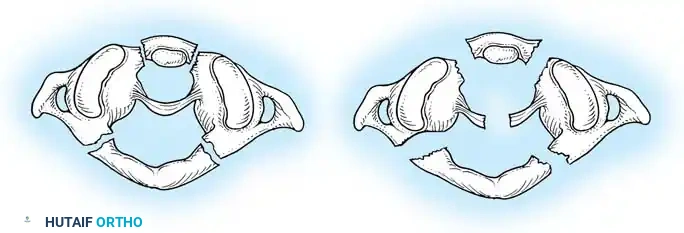

Fig 2. Diagrammatic representation of facet subluxation and dislocation mechanics.

* Stage 1: Failure of the PLC, evidenced by facet subluxation in flexion and abnormal divergence of the spinous processes (widened interspinous distance).

* Stage 2: Unilateral facet dislocation. Subluxation of the contralateral facet suggests severe ligamentous injury. Beatson's serial sectioning studies demonstrated that unilateral dislocation can occur with rupture of only the posterior interspinous ligament and the facet capsule.

* Stage 3: Bilateral facet dislocations, presenting with approximately 50% anterior subluxation of the vertebral body. This requires complete rupture of the interspinous ligament, both facet capsules, the posterior longitudinal ligament (PLL), and the annulus fibrosus.

* Stage 4: Full vertebral body width displacement anteriorly. This creates a grossly unstable motion segment, often termed a "floating" vertebra.